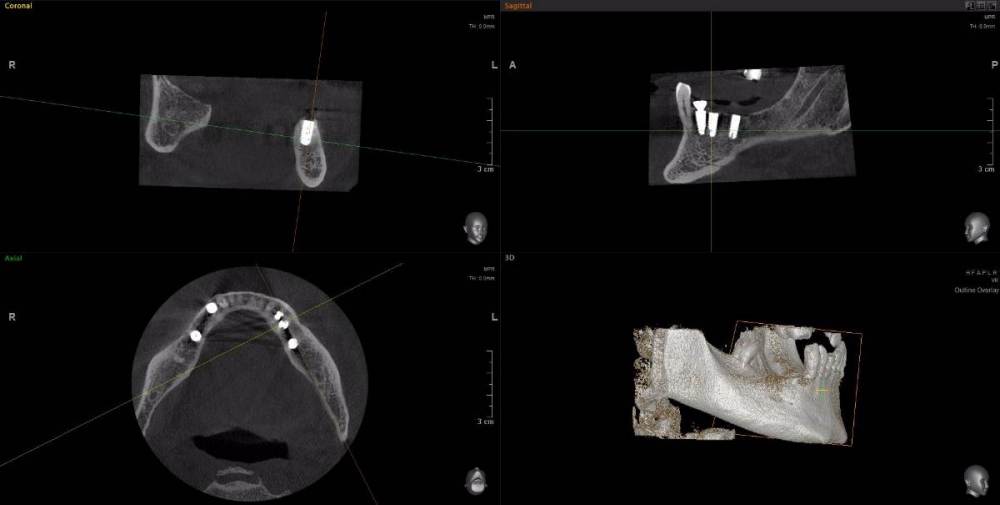

m-art-a23 Опубликовано 21 апреля, 2021 Поделиться Опубликовано 21 апреля, 2021 Здравствуйте. Два дня назад мужу установили 5 имплантов Ankylos на нижнюю челюсть (2+3). Спустя 30-40 мин после операции появилась сильная острая боль, которая не уменьшается по настоящее время. Боль похожа по ощущениям на пульпитную, не снимается никакими НПВС, кроме кеторолака. А/б, А/гистаминные, холод местно, хлоргексидин - все рекомендации выполнялись. На осмотре врачом не обнаружено следов воспаления, КТ сделал - без особенностей. Что может служить причиной такой боли, сколько она может длиться и что делать в данной ситуации? Врач-имплантолог ничего внятного не предложил. Ссылка на КТhttps://cloud.mail.ru/public/EvKn/ULqxLy6BD Ссылка на комментарий

red_butler Опубликовано 22 апреля, 2021 Поделиться Опубликовано 22 апреля, 2021 7 минут назад, m-art-a23 сказал: Нет, не один. Но он лучший. Скажите пожалуйста, что служит причиной боли, по-Вашему? Неужели все импланты нужно убирать только по Кт трудно судить, но есть вопросы по позиционированию имплантов... боль может быть вызвана перегревом кости во время формирования ложа импланта, но в этом случае она появляется примерно с третьего дня. Так же боль может вызывать гиперкомпрессия импланта, и может болеть кость если ее придавили формирователем десны. Я бы обсудил с хирургом удаление среднего импланта слева 1 Ссылка на комментарий

Irouil Опубликовано 22 апреля, 2021 Поделиться Опубликовано 22 апреля, 2021 Я бы рекомендовал удаление среднего импланта слева, независимо от наличия/отсутствия болевых ощущений боль может быть признаком каких-то описанных моим коллегой процессов, а может ничего кроме самой боли не означать (менее вероятно, но и такое бывает). Если удаление упомянутого импланта поможет против болевого синдрома - это win-win если хирург не видит необходимости удаления импланта, я бы рекомендовал сходить на осмотр к ортопеду, который будет в будущем эти импланты протезировать. Возможно у него найдутся весомые аргументы для коллеги 3 Ссылка на комментарий

Irouil Опубликовано 22 апреля, 2021 Поделиться Опубликовано 22 апреля, 2021 (изменено) 1 час назад, m-art-a23 сказал: Благогдарю за совет. Если Вам не трудно, объясните пожалуйста, что не так со средним имплантом. Описанные процессы, если таковые имеют место быть, должны постепенно прийти в норму? Другими словами, сколько еще нужно времени, чтобы окончательно принять решение об удалении импланта (имплантов)? Сегодня третьи сутки после установки. Боль сохраняется. Средний имплант расположен чрезвычайно близко к соседнему, расположенному кпереди от него. С очень большой долей вероятности это может привести к значительной резорбции (убыли) костной ткани между ними, что для любых имплантов очень вредно, а для конкретно Анкилосов - губительно из-за особенностей их протезирования. Если неблаготворные процессы (компрессионный или термический некроз) присутствуют, то импланты просто не интегрируются (не приживутся) - те, что зашиты не выдержат нагрузки при раскрытии, а тот, на котором стоит ФДМ - расшатается через 2-3 недели. Это не призыв проверять его стабильность языком, сейчас его лишний раз лучше не трогать. В норме после имплантации боли держатся 1-2 дня, если все не очень хорошо - держатся 2-3 недели, но даже в таком случае имплант может интегрироваться, поэтому решение об его удалении в таком случае должно, по моему убеждению, быть совместным между врачом и пациентом, и приниматься в индивидуальном порядке Изменено 22 апреля, 2021 пользователем Irouil Ссылка на комментарий